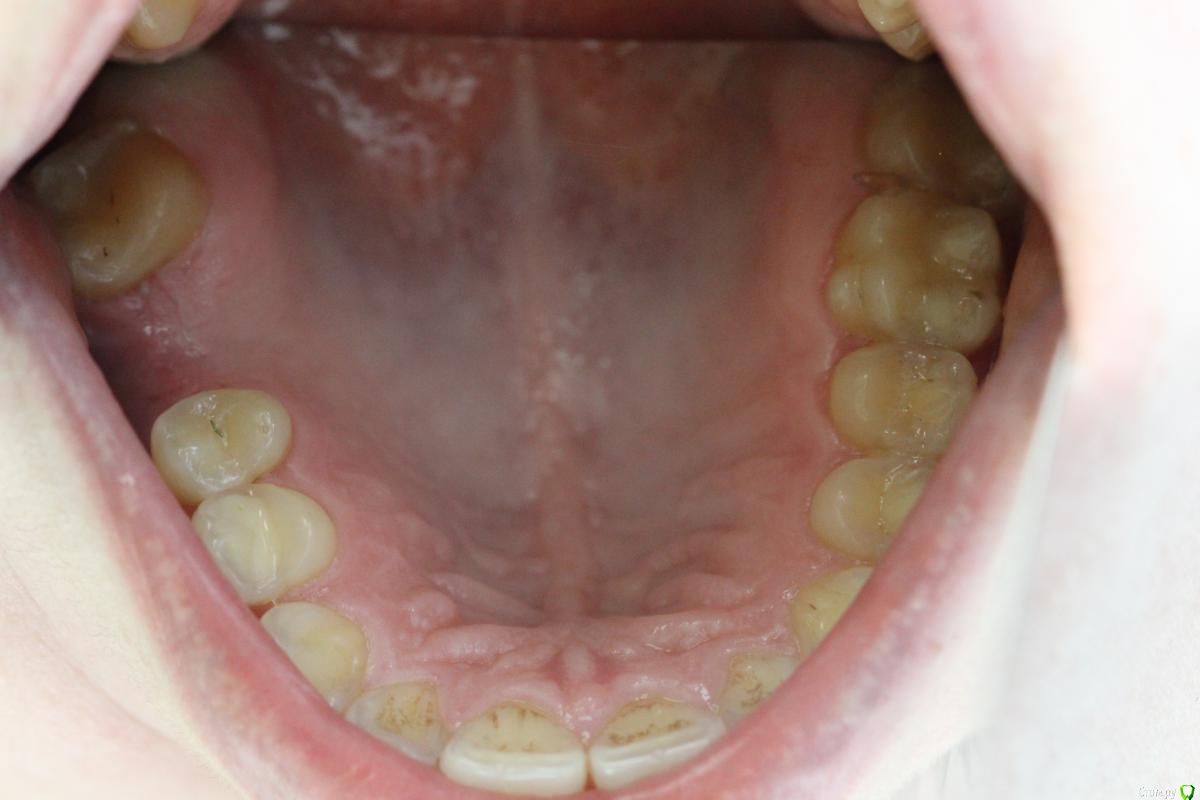

Norton Опубликовано 14 апреля, 2019 Поделиться Опубликовано 14 апреля, 2019 (изменено) Доброго времени суток уважаемые коллеги. Ко мне обратилась пациентка с установленным импл. в области верхней 6 (XIVE 3.8 / 11 мм). Сейчас назревает вопрос нужна ли мягкотканная пластика или нет? Cмутило то, что несколько коллег в моем городе порекомендовали сделать. Изменено 14 апреля, 2019 пользователем Norton Ссылка на комментарий

Norton Опубликовано 17 апреля, 2019 Автор Поделиться Опубликовано 17 апреля, 2019 (изменено) Покажите фото внутриротовоеФото Изменено 17 апреля, 2019 пользователем Norton Ссылка на комментарий

Aquarius Опубликовано 15 апреля, 2019 Поделиться Опубликовано 15 апреля, 2019 Думаю, имплант надежен в плане долгосрока. Коллагена с небной стороны вагон 3 Ссылка на комментарий

Дмитрий М Опубликовано 18 апреля, 2019 Поделиться Опубликовано 18 апреля, 2019 (изменено) отлом вестибулярной или миграция графта?похоже свободный фрагмент, пальпируется нет? Изменено 18 апреля, 2019 пользователем Дмитрий М Ссылка на комментарий

Magadalina Опубликовано 19 апреля, 2019 Поделиться Опубликовано 19 апреля, 2019 Похоже на выход графта сразу после синус- лифтинга через окно. Это никакого значения не имеет Ссылка на комментарий